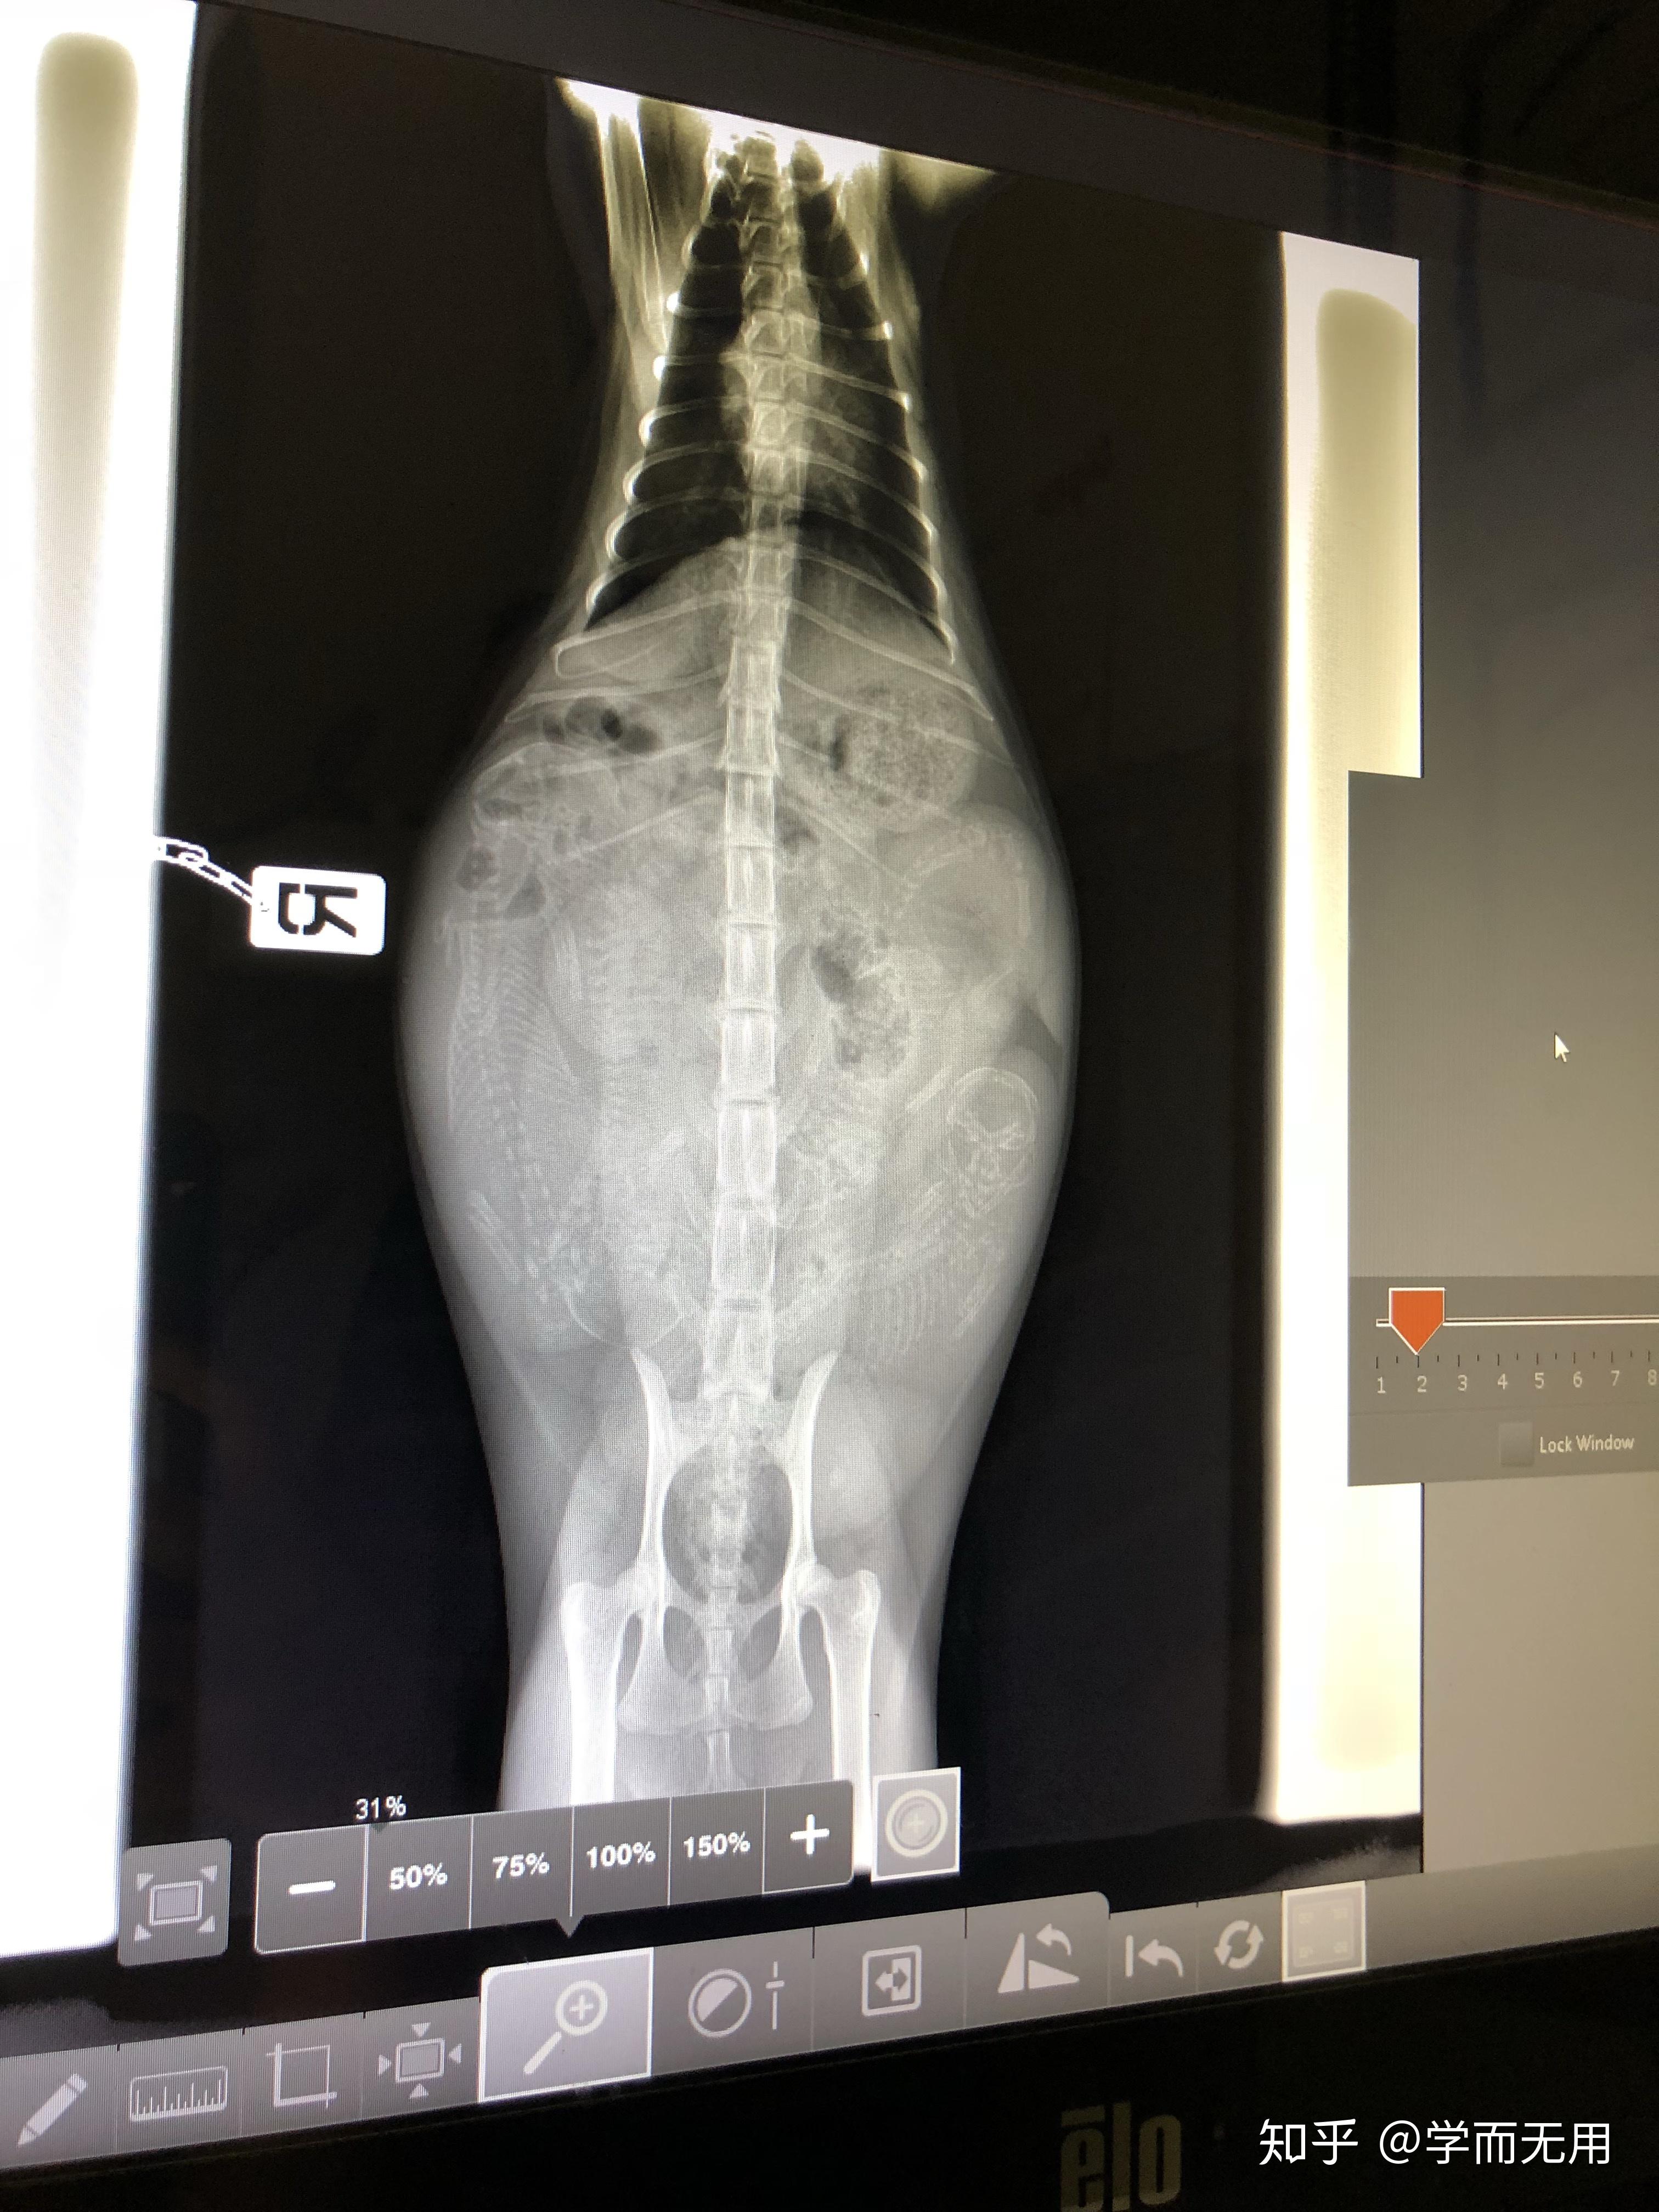

她肚子突然就鼓了!乳头也变得突出了!虽然不是很明显,但是作为敏感的老母亲,我赶紧带她去了医院,预约了b超。

这一b超不要紧,妈呀,竟然肚子里藏了4个宝宝!

知道有4个以后,还是很震惊的嘛。因为我家妞妞体型太娇小了,难以想象她怀了一肚子娃。

医生说四个猫崽发育很均衡哦。